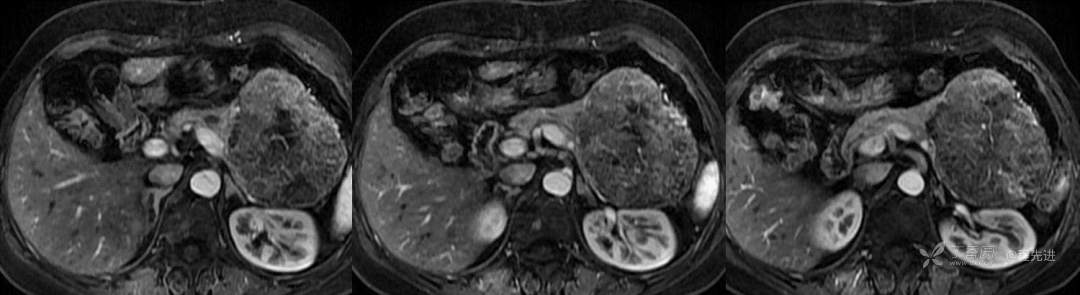

动态增强

动脉期

门脉期